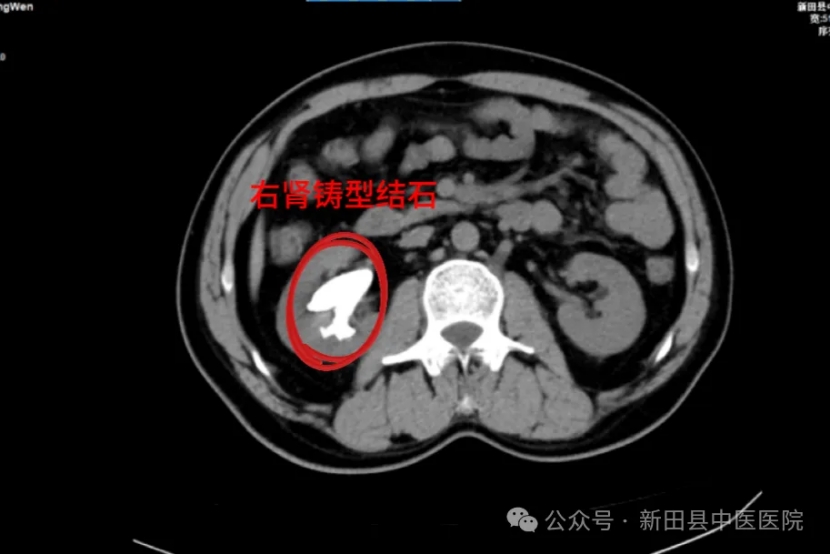

前段时间,55岁的陈女士在体检时,被查出右肾多发结石,且结石形似“鹿角”,属于典型的“铸型结石”。 真是“不查不知道,一查吓一跳!”

带着这些疑问,陈女士慕名到新田县中医医院找泌尿外科邓勇军主任求诊。邓勇军详细询问陈女士病史并进行了仔细体查,结合其检查报告“右肾多发结石,其中最大结石约40x27mm”,建议陈女士住院行手术治疗,并告诉她,肾脏巨大铸型结石是比较严重的,继续发展会导致肾脏积水,肾功能不全。

▲术前CT

邓勇军介绍,铸型结石是泌尿系统结石中最难处理的结石,由于患者右肾多发铸型结石大且过于分散,很难通过一次手术彻底将结石完整取出。这种结石深入到肾盂肾盏,空间比较狭小,因此碎石的时候要特别小心,既要粉碎并取出结石也要防止钬激光伤及周围组织,激光的能量控制要格外注意。同时患者肾脏完全无积水,穿刺建立通道困难且易于出血,稍有不慎则肾脏难以保全。